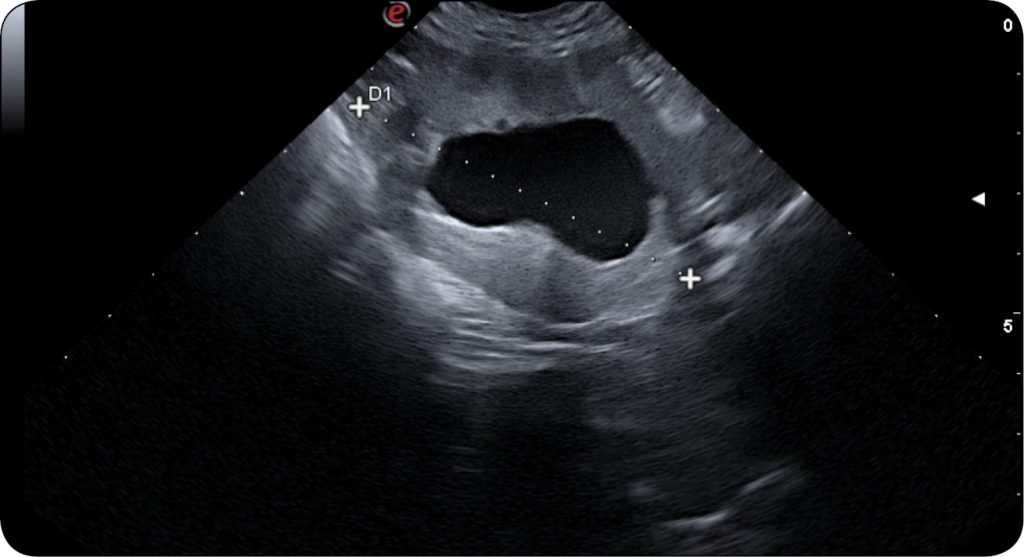

Do typowych objawów klinicznych związanych z chorobą układu moczowego zalicza się: częstomocz, strangurię, krwiomocz, periurię, wokalizację, wyłysienie okolicy pachwinowej na skutek wylizywania. Objawy są wspólne, ale ich przyczyny mogą być zupełnie różne. Do najczęstszych chorób układu moczowego u psów i kotów zalicza się: ZUM (zakażenie układu moczowego), kamicę układu moczowego, idiopatyczne zapalenie pęcherza moczowego, nowotwory (najczęściej TCC), wady rozwojowe. Nierzadko choroba podstawowa ma dodatkową komponentę – np. nowotwór pęcherza moczowego może być powikłany przez wtórne zakażenie bakteryjne.

Zakażenia układu moczowego u psów zdarzają się stosunkowo często. Szacuje się, że 5-27% psów w trakcie swojego życia choruje na ZUM, a bardziej podatne są samice. Grupę podwyższonego ryzyka stanowią zwierzęta starsze oraz młode. ZUM może być konsekwencją chorób ogólnoustrojowych oraz farmakoterapii, np. sterydoterapii. Ponadto znacznie częściej spotykany jest u zwierząt z różnymi wadami rozwojowymi dróg moczowych, takimi jak ektopia moczowodu/-ów czy JKD (ang. juvenile kidney disease).